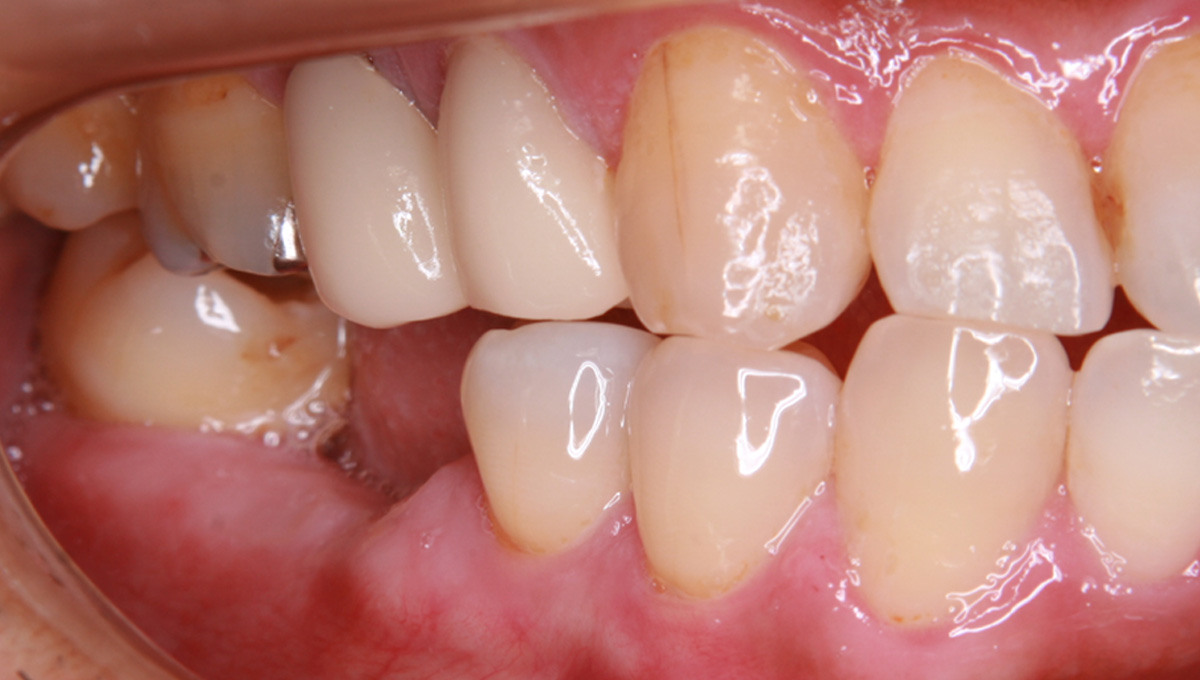

インプラント手術から3ヵ月後、型どりをして、仮歯を製作しました。

レントゲン画像 -

仮歯の調整期間を経て、セラミックの歯が入りました。

レントゲン画像 治療前 インプラント治療後